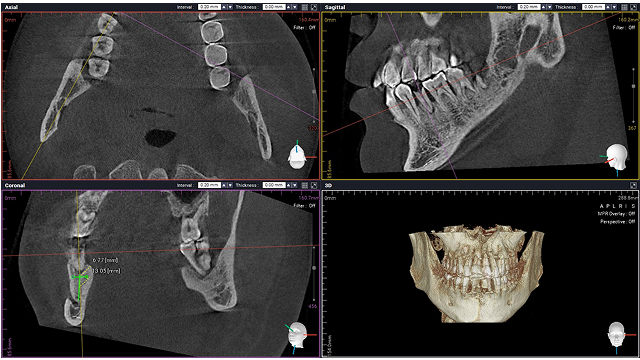

이숲치과에서는 정밀 영상 진단(CT, 파노라마)을 통해

사랑니의 위치·신경 관계·난이도를 정확히 파악한 뒤,

통증과 부기를 최소화하는 수술 방식으로 안전하게 발치를 진행합니다.

CT 촬영 엑스레이 사진

CT 기반 정밀 진단으로 신경손상 위험 최소화